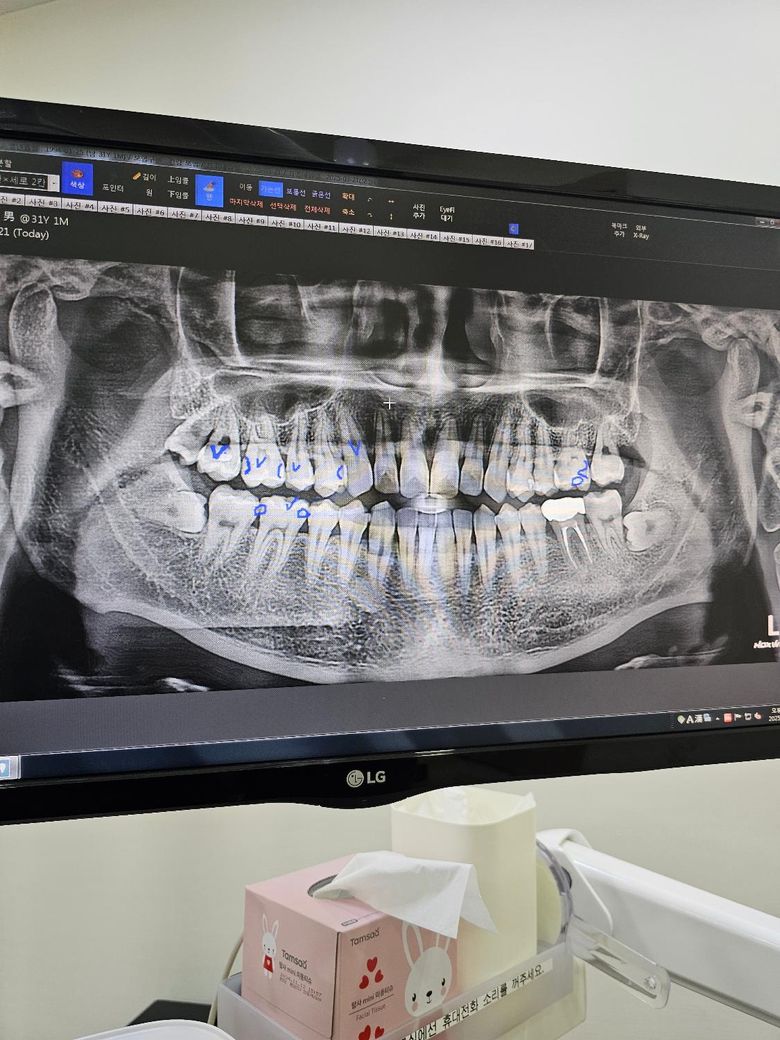

사이충치 인접면충치 과잉진료인지 확인부탁해요

차과에 갔는데 사이충치 인접면충치가 엄청많다고 합니다 견적은 크라운5개 인레이3개 레진4개 잇몸치료 그리고 사랑니발치 1개 이고 차료비합계는 340만원정도에요

그리고 인레이 3개중 2개는 크라운을 권장한다고 하셨어요

전체적으로 치아 사이에 충치가 많은거 같습니다. 치료방법은 치과의사마다 다르긴 하지만 양쪽에 충치가 다 잇어서 크라운 치료를 권유하신게 아닐까 생각됩니다.

해당 사진은 파노라마 사진이고 정확한 인접면 충치 체크를 위해서는 치근단 사진, 교익 사진이 필요합니다.